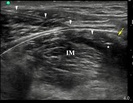

Wobec doświadczeń dotyczących anestezji przewodowej przez igłę, cewniki zakładane pod kontrolą ultrasonografii z dostępu podobojczykowego przedstawiane są jako zapewniające lepszą analgezję, niż te zakładane z dostępu nadobojczykowego. Technika podawania bolusa przez cewnik, która niewątpliwie „sprawdza” skuteczność cewnika przed rozpoczęciem ciągłej infuzji została zbadana dla cewników zakładanych z dostępu podobojczykowego, ale nie dla dostępu nadobojczykowego. Poniższe badanie ocenia technikę podawania bolusów przez cewnik zakładany z dostępu nadobojczykowego i weryfikuje hipotezę, iż cewnik zakładany z dostępu podobojczykowego zapewnia szybszy początek wystąpienia blokady splotu barkowego.

więcejPorównanie skuteczności cewników okołonerwowych zakładanych z dostępu pod i nadobojczykowego celem anestezji przewodowej w powtarzanych bolusach przez pozostawiony cewnik.

Blokada splotu ramiennego z dostępu pachowego najczęściej wykonywana jest przy pomocy ultrasonografii, ale alternatywne metody znajdują swoje zastosowanie, gdy brak jest dostępu do aparatury USG. Kwestionuje się obecnie konieczność trzech iniekcji przy blokadach z dostępu pachowego bez użycia ultrasonografii

więcejMRI blokady splotu ramiennego z dostępu pachowego: badanie randomizowane